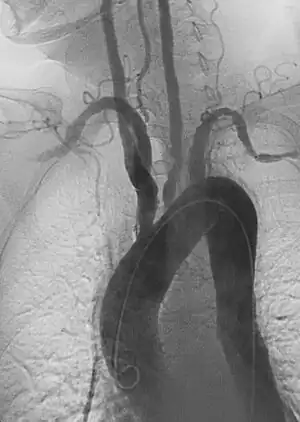

- Angiography: Sometimes referred to as traditional angiography, catheter angiography or digital subtraction angiography (DSA). A small needle is inserted into a blood vessel, then exchanged for a catheter over a wire. The catheter is directed at the vessel to be studied, and contrast is directly injected to evaluate the lumen under video X-ray. This is an older technique than modern CT angiography or MR angiography, but provides unique advantages. With a catheter in place, provocative maneuvers can be performed such as breath holds or instillation of vasodilators, to evaluate a patient's blood flow dynamically. This can reproduce symptoms and identify functional abnormalities in a vessel that a static CT or MR imaging cannot.[79][80] Angiography provides the basis for all endovascular therapy.

There are several systems for staging PAD, but an often used scale is the revised Rutherford classification.[75][88] Plaque and blood flow can be evaluated using ultrasound, CT angiography, MR angiography, and catheter-based angiography to establish anatomic segments of disease. The severity of ischemia can be evaluated by correlating symptoms and non-invasive physiologic vascular studies including toe pressures, TCPO2, and skin perfusion studies.